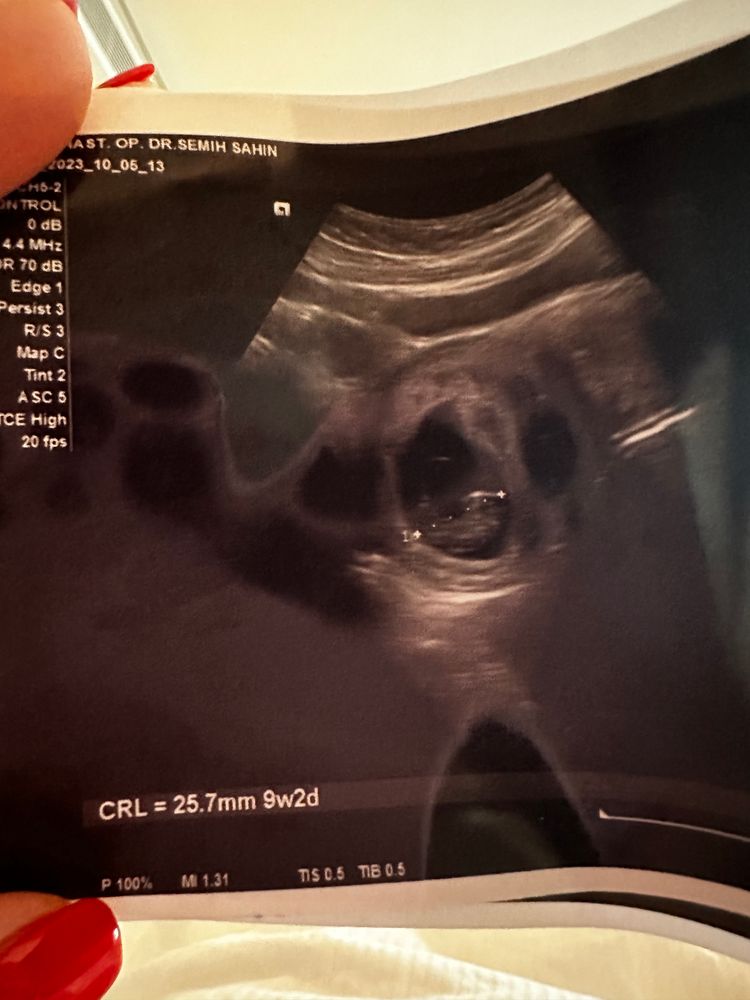

Алисия, один и тоже же и аппарат один, там на экране рост видно. Вот картинки Изображение Изображение